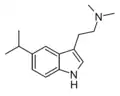

| 5-Isopropyl-DMT | artificial | 5-CH(CH3)2 | CH3 | CH3 | 5-isopropyl-N,N-dimethyltryptamine | 156281-04-8 |